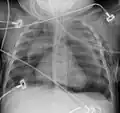

Pneumomediastinum is uncommon and occurs when air leaks into the mediastinum. The diagnosis can be confirmed via chest X-ray showing a radiolucent outline around the heart and mediastinum or via CT scanning of the thorax.

Pneumomediastinum and right sided pneumothorax post first rib fracture in a mountain biking accident.